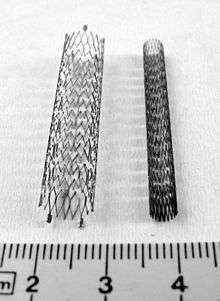

| Vascular stents are commonly placed as part of peripheral artery angioplasty. Common sites treated with peripheral artery stents include the carotid, iliac, and femoral arteries. Because of the external compression and mechanical forces subjected to these locations, flexible stent materials such as nitinol are used in a majority of peripheral stent placements.[1] |  Compressed and expanded peripheral artery stents |